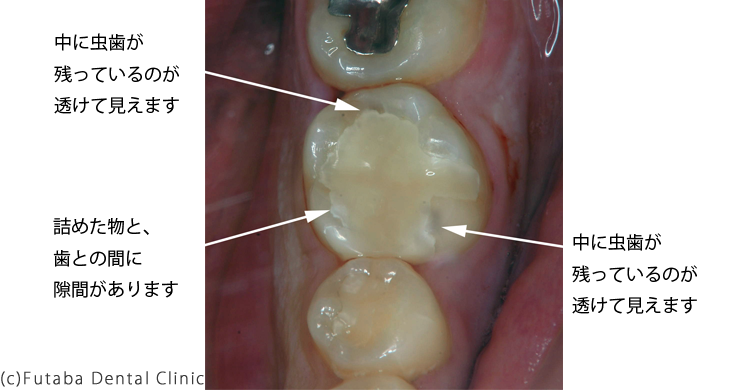

お口の中の状況ですが、

詰め物は、全く適合していない

中に虫歯がまだ透けて見える状態でした。